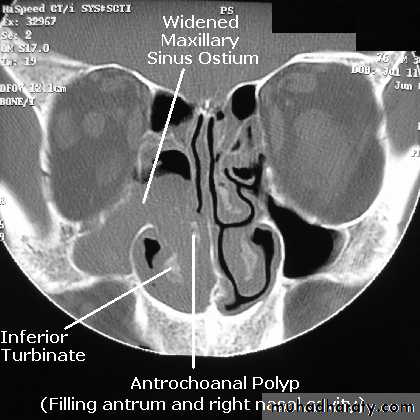

Antrochoanal polyps

These polyps arise from the lining of the maxillary sinus and prolapse through the ostium in the middle meatus and extend backwards through the posterior choana to the nasopharynx. The choanal part of the polyp may be seen in the oropharynx.

The polyp tend to be dumb-bell in shape with a constriction where they pass through the ostium of the sinus.

They are often unilateral but may cause bilateral nasal obstruction by expanding into the entire nasopharynx. The classical presentation is a good inspiratory airway with blockage on expiration. This is the result of ball-valve effect of the polyp blocking the posterior choana.

Anterior rhinoscopy may look normal as only a thin stalk may be present in the nose. The enlarged posterior end may only be seen on posterior rhinoscopy.

Radiography of the maxillary sinus will show complete opacification of the affected antrum.